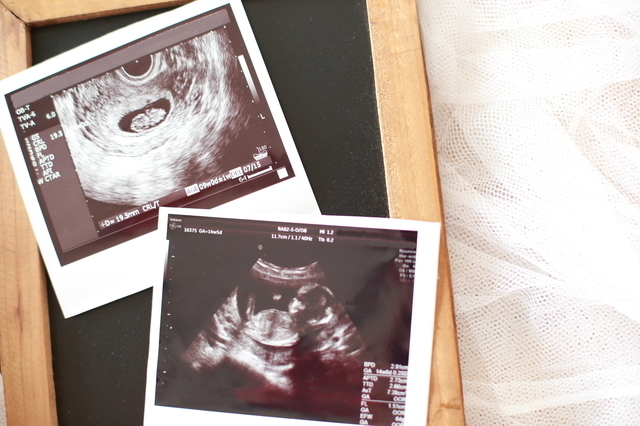

赤ちゃんの心拍確認がとれ、超音波(エコー)検査では頭、胴、足がはっきりと分かれて手が見える姿も確認することができ、赤ちゃんの成長を実感するママも多いです。

妊娠9週の胎児は体の大きさも30mm程度に成長して体重も3g~12gくらいになります。指も1本ずつ離れてきます。心臓もほとんど完成して赤ちゃんの心拍音も力強く聞こえるようになるでしょう。

軟骨はありますが骨はまだなく、胎児の脳がエコーで見えることもあります。